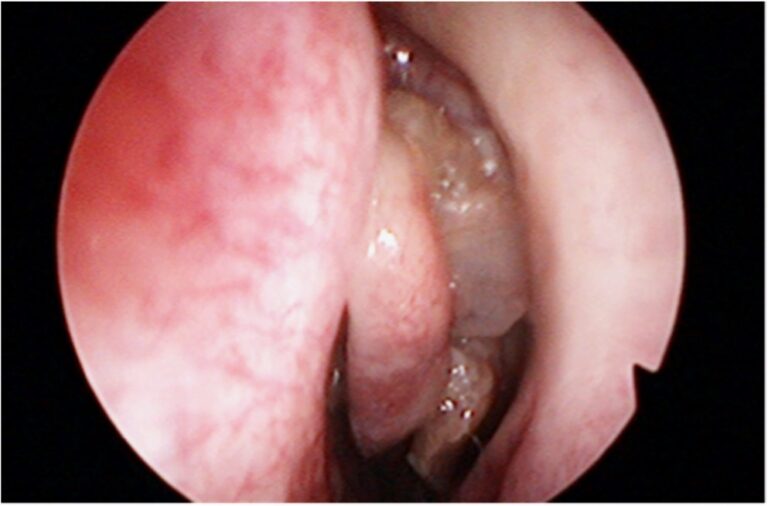

Sinusite batterica monolaterale: maxillectomia mediale endoscopica modificata

Sinusite Acuta Monolaterale: trattamento endoscopico rinosinusale

Maxillectomia mediale endoscopica per papilloma invertito del seno mascellare

Papilloma invertito rinosinusale e recidive

Patologia Rinosinusale Monolaterale